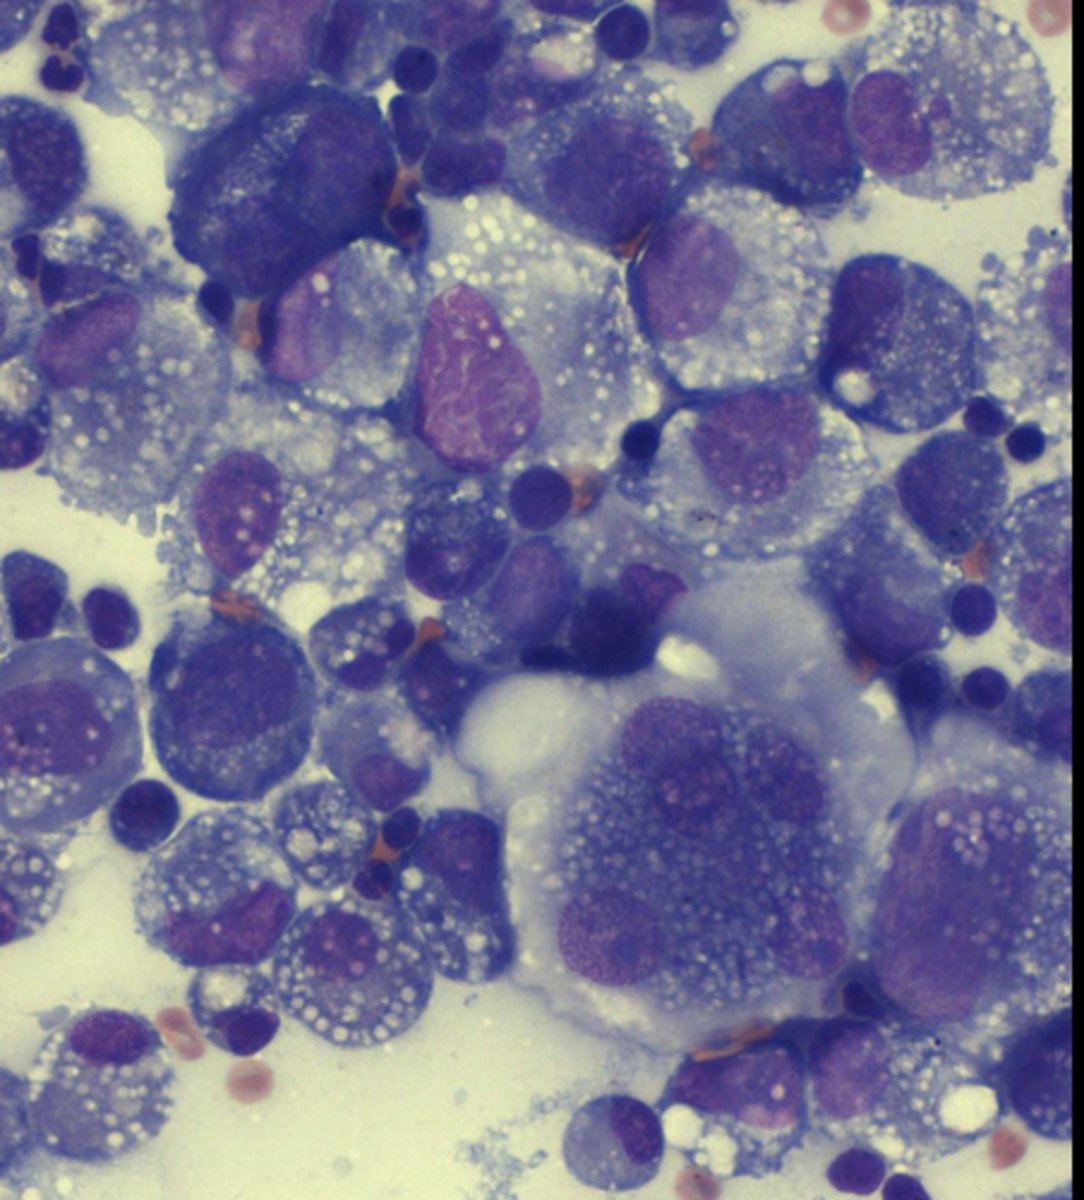

Histiocytic Sarcoma

What type of round cell tumor is this?

-Sheets of large, pleomorphic, mononuclear and multinucleated giant cells

- Can appear as spindle-shaped cells

- Abundant basophilic cytoplasm with vacuoles, may see phagocytosis of RBCs/WBCs